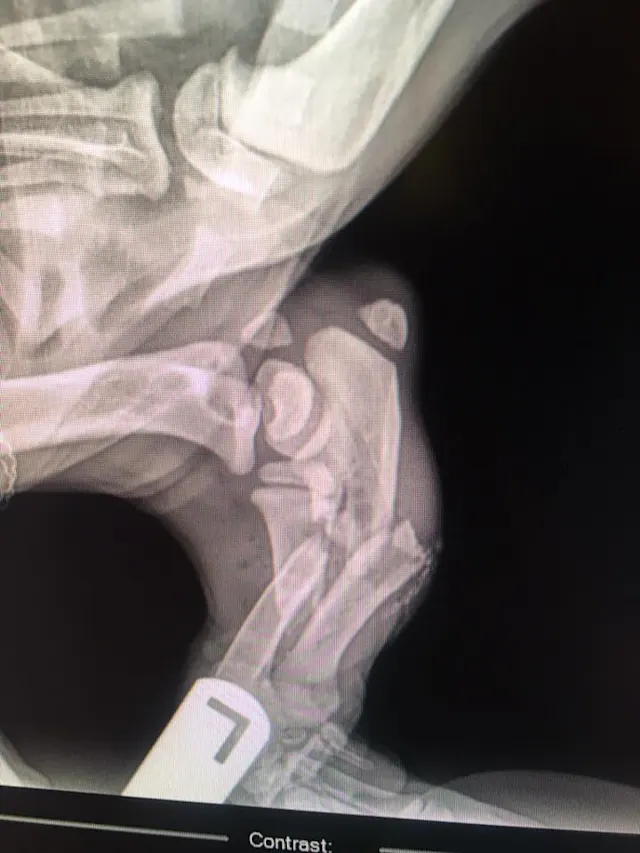

"This energetic 10-month-old Labrador swallowed a 12-inch serrated knife. The puppy was bouncing off the walls when he was brought in and it was hard to keep him still. Surgery went well and amazingly, nothing was damaged!"—Katelyn E